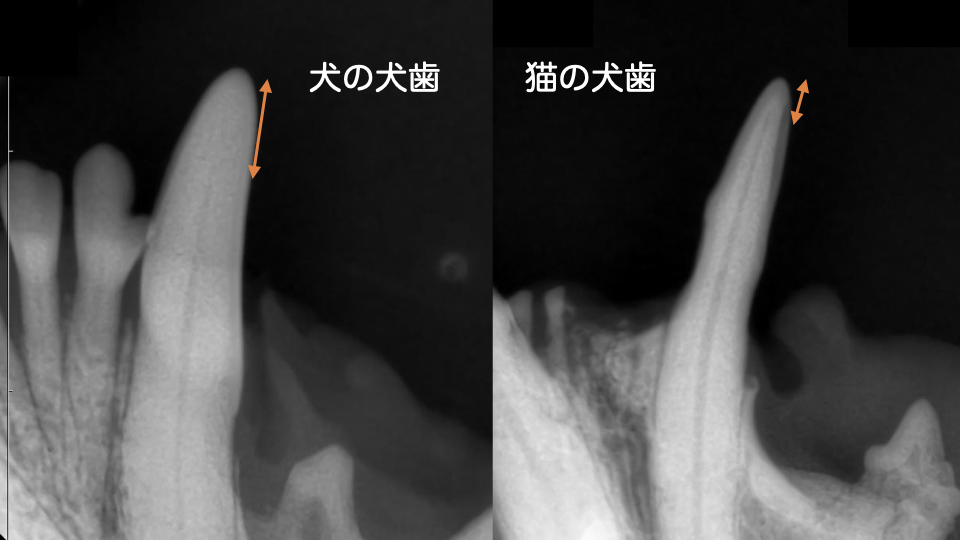

特に猫の犬歯は犬と異なり先端まで歯髄腔が通っているため、わずかに折れただけでも露髄してしまいます。

(オレンジ矢印が先端から歯髄腔までの距離)